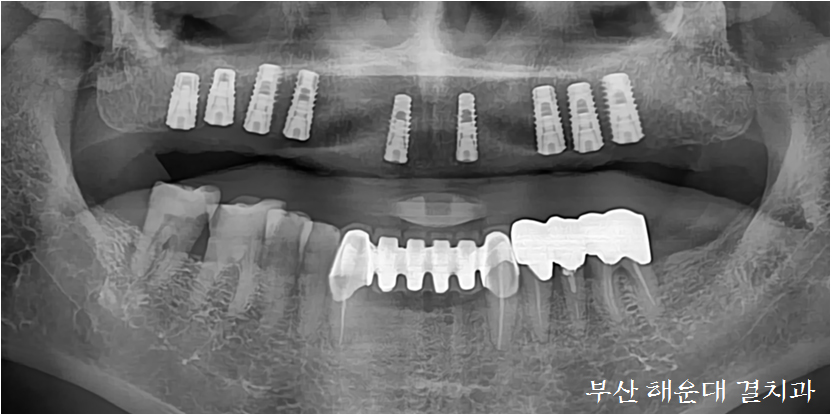

식립 후 사진(좌)과 CT분석(우)에서의 사진을 비교해 보면 거의 동일한 위치에 임플란트가 정확히 식립되어 있는것을 볼 수 있습니다. 해운대 결치과는 대학병원에서 임플란트 수술을 전문으로 많은 수술경험을 갖고 있기 때문에 안심하고 수술을 받으시면 됩니다!

수술에 소요된 시간은 1시간 30분 이내로, 빠른 시간 내에 수술이 완료되어 통증과 출혈을 최소화 하였습니다. 해운대 결치과에서는 수술 전에 정밀한 수술가이드 제작, CT촬영, 정확한 분석과 컴퓨터가상수술을 시행하기 때문에 짧은 수술시간안에 정확한 위치에 다수 임플란트를 식립 가능합니다.